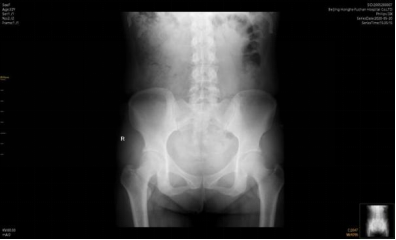

但总体一个原则,这些医生是有行医资格的,并且西医医生还会要求在治疗之前看骨盆的X光片。